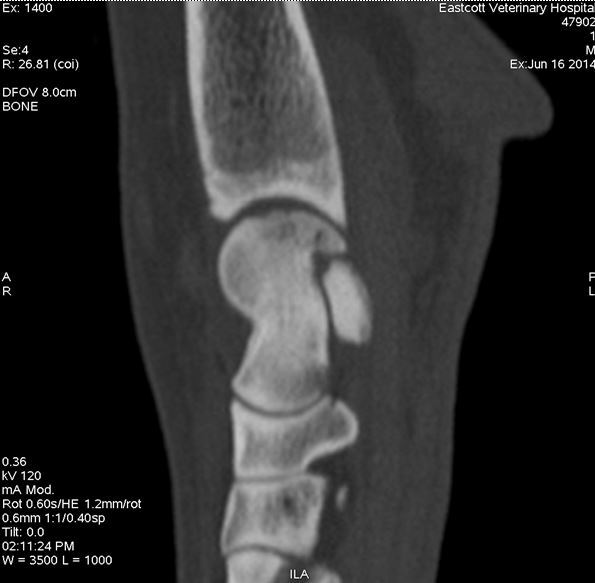

Sagittal image of hock showing OCD lesion of the medial talar ridge

Figure 1